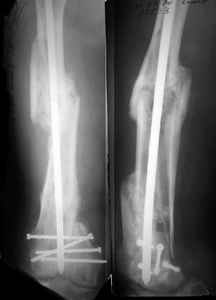

1. Percutaneous nailing is truly minimally invasive technique, but, unfortunately, nails are not reliable in many hands.

Attached are few examples from our Hospital:

A. Difficult reductions, even in retrograde nailing (my preference, easier control of "small" distal fragment) and it is much, much harder to do it anterograde (Alex, do you have one good case in your collection of anterograde nailing in very distal fractures - as you have suggested that I

should have done it in my previously posted case?

Malpositioning is much too common (recurvatum, varus - valgus).

B. Fixation loosening: distal cutting of the nail, non-unions do happen (cases attached).

Locking Plating has more distal screws than any nail, fixed angles and provides much better fixation, especially in osteoporotic bone.

A new toy is more interesting and fashionable. And anyway it is not panacea, i have already seen presentations with LISS failures like the attached one presented by D.Seligson. And people also demonstrated incisions say that the method is not so LESS invasive as it supposed to be.